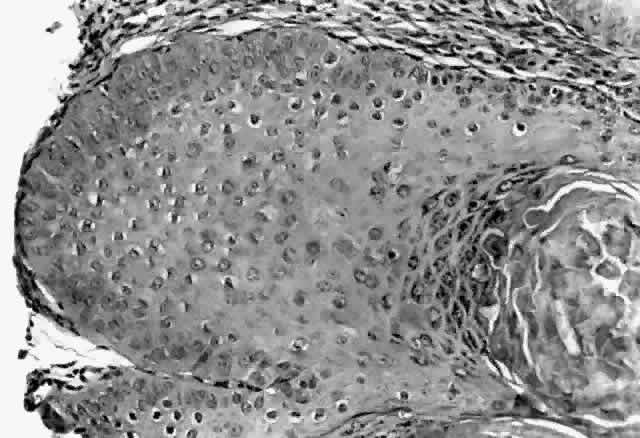

HPV-induced conjunctival squamous papillomas demonstrate papillomatosis, acanthosis, and koilocytosis (Fig. 6). Because they are mucous membrane lesions, those of the conjunctiva and lacrimal sac show no granular cell layer but will show keratinization if they are large or exposed (Fig. 7). In our experience the frequency of koilocytes is variable, even in lesions almost certain to be viral (Fig. 8). Scattered inflammatory cells may be present in the cores or epithelium. Virus can be detected immunohistochemically in the nuclei of the cells (Fig. 9).

Fig. 6. Eyelid papilloma, histology. High-power view of acanthotic epithelium and koilocytes. (Original magnification × 400)

Squamous papillomas of the eyelid are exophytic lesions with multiple fronds, each showing acanthotic epithelium around a fibrovascular core. There is typically hyperkeratosis and koilocytosis. Inflammatory cells may be present.